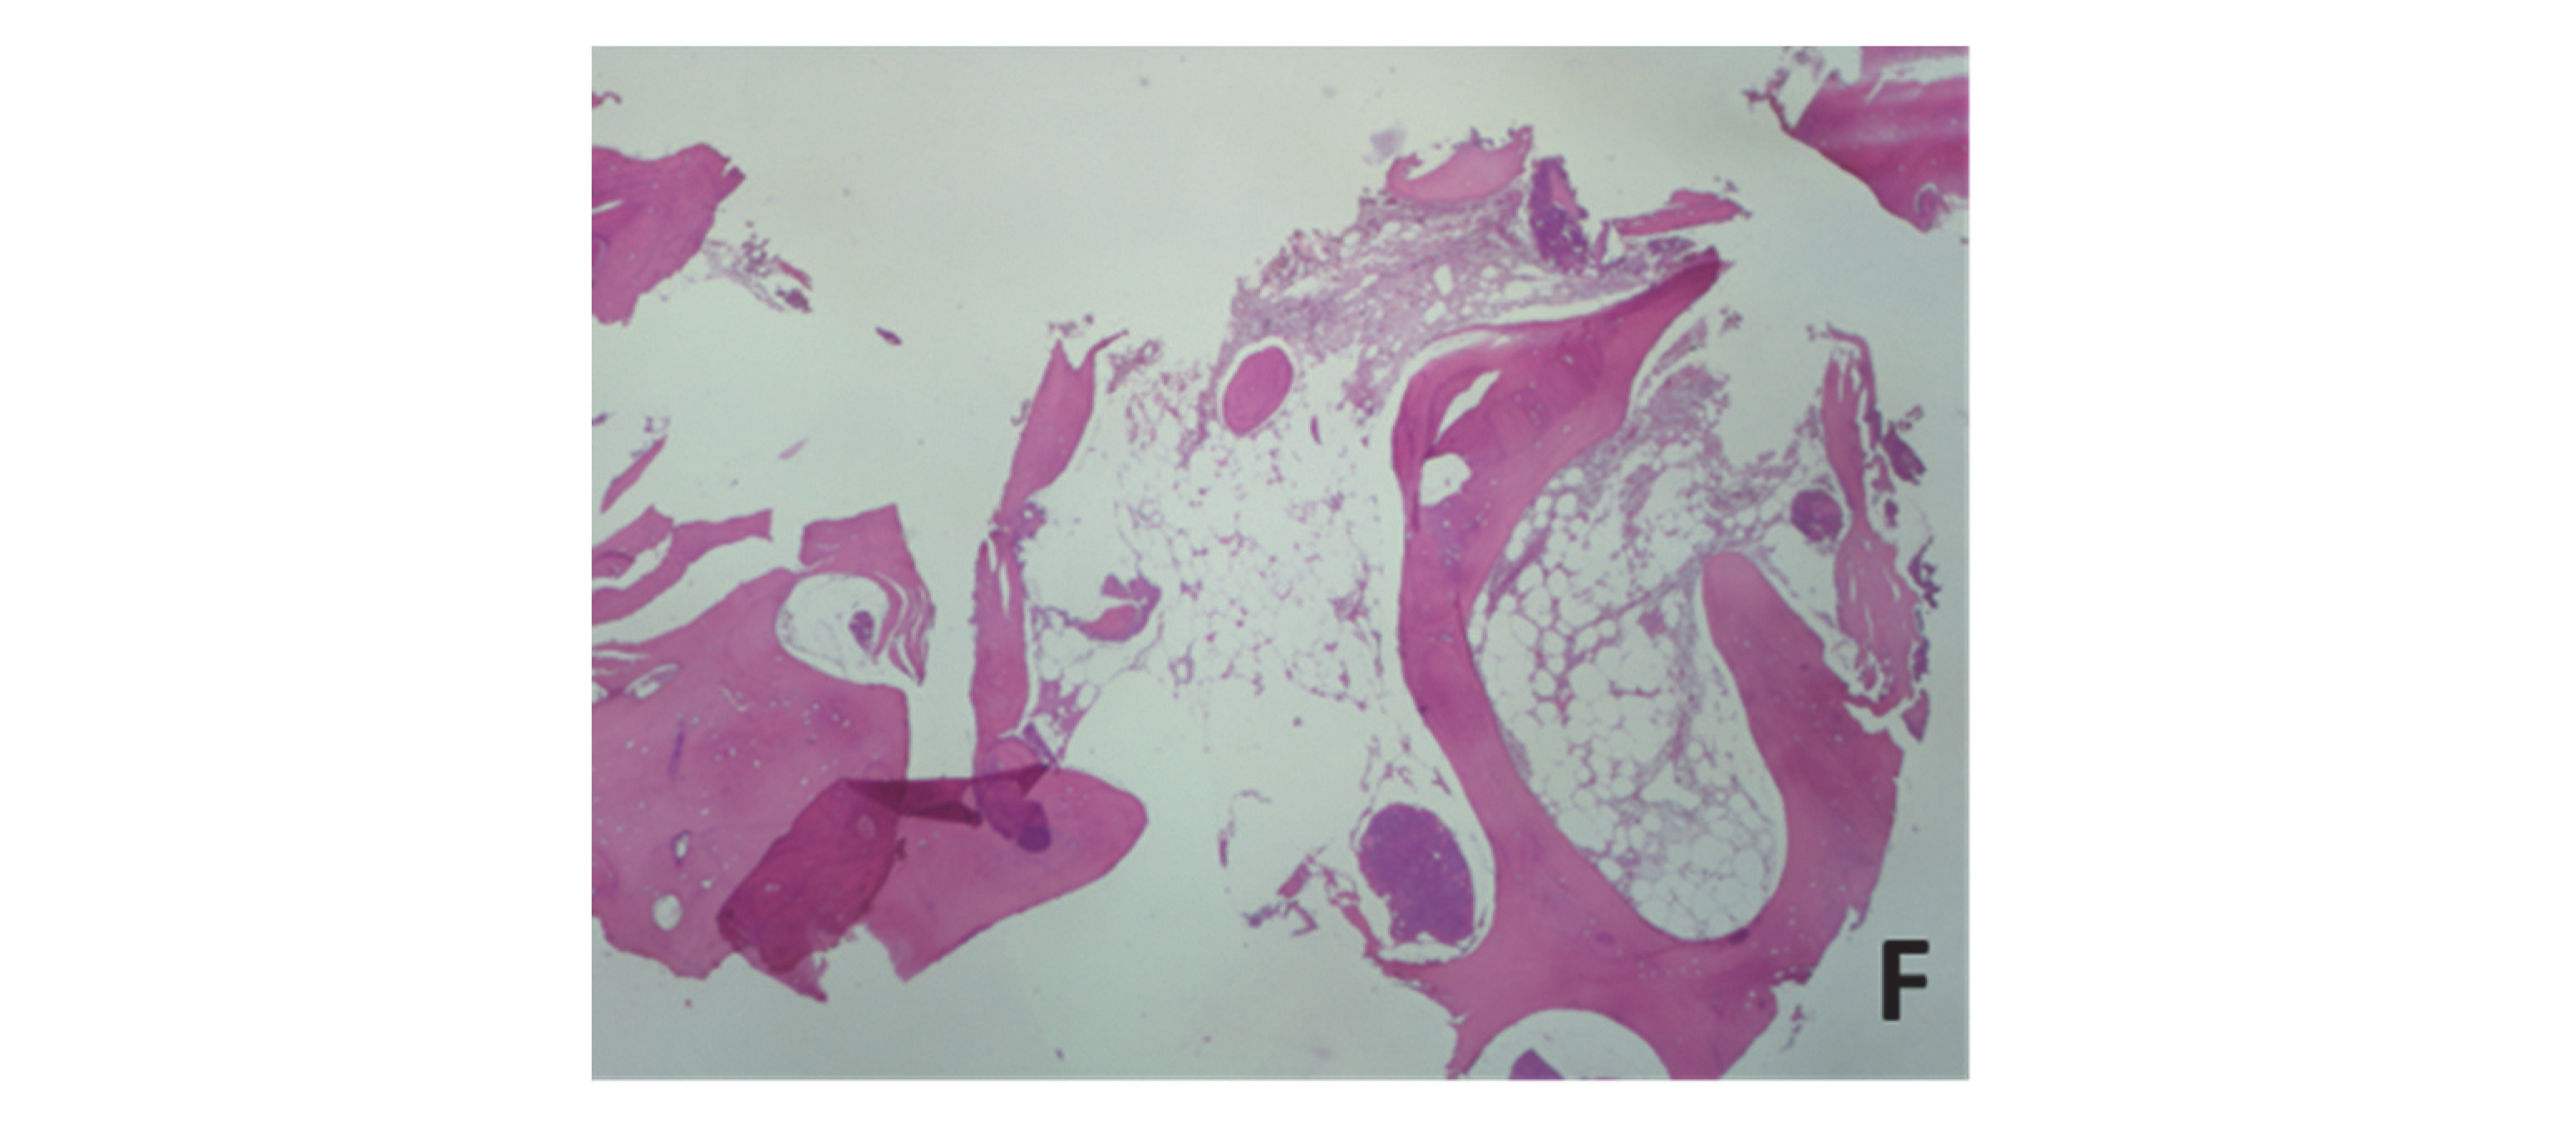

From musculoskeletalkey.com

Parosteal Osteoma Musculoskeletal Key Osteoma Dentistry Definition An osteoma is actually a hamartoma, an abnormal proliferation of compact bone without stromal cellular. Osteomas show very slow continuous growth, even in adulthood, unlike other bony lesions. an osteoma is a benign bone craniofacial lesion with a slow growth rate, mainly affecting the mandible. Depending on where they develop, osteomas can sometimes cause symptoms such as headaches or. Osteoma Dentistry Definition.

From www.oooojournal.net

Mandibular traumatic peripheral osteoma a case report Oral Surgery Osteoma Dentistry Definition An osteoma is actually a hamartoma, an abnormal proliferation of compact bone without stromal cellular. an osteoma is a benign bone craniofacial lesion with a slow growth rate, mainly affecting the mandible. an osteoma is a benign bone lesion with no clear pathogenesis, almost exclusive to the craniofacial area. an osteoma is a benign bone tumor that. Osteoma Dentistry Definition.

From www.mdpi.com

Dentistry Journal Free FullText Peripheral Osteoma of the Osteoma Dentistry Definition osteoma is a benign neoplasm characterized by proliferation of either. Osteomas show very slow continuous growth, even in adulthood, unlike other bony lesions. An osteoma is actually a hamartoma, an abnormal proliferation of compact bone without stromal cellular. Depending on where they develop, osteomas can sometimes cause symptoms such as headaches or sinus. an osteoma is a benign. Osteoma Dentistry Definition.